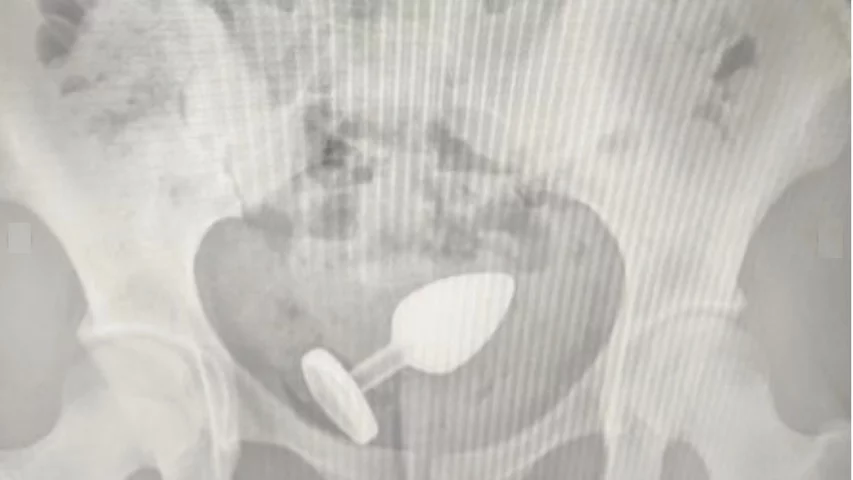

Saúde Paula Aguiar brinquedos eróticos, dicas de uso, educadora sexual, plug anal, prazer seguro, saúde íntima, segurança 0 Comentários Uso de Plug Anal Leva Paciente ao Hospital